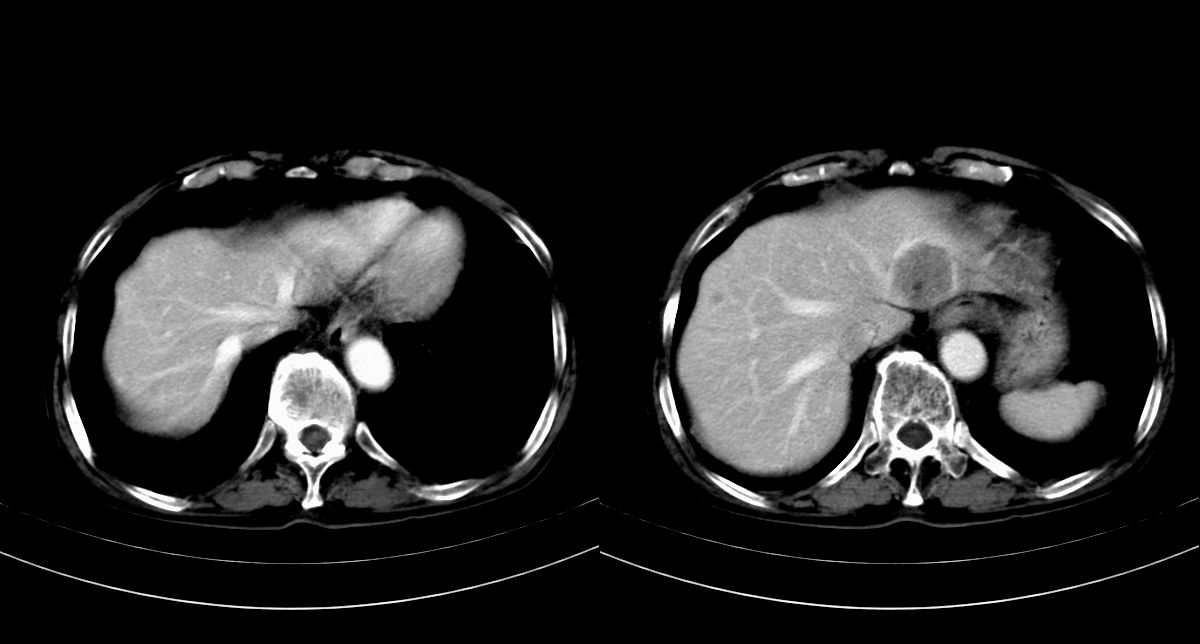

男,79y,无不适。体检发现肝脏占位。

肝内多发低密度结节,增强动脉期明显强化,门脉期逐渐下降,内有液化坏死区。

诊断:

肝细胞癌(结节型)

鉴别:肝转移癌。

肝内多发低密度结节灶,增强动脉期明显不规则环状强化,;门脉期逐渐下降,肿瘤壁厚薄不一,内有坏死液化区。

诊断:肝转移癌可能

鉴别:1原发性肝癌(强化方式符合,建议查afp)

巨块型肝癌伴肝内转移.

肝癌并肝内转移。

肝癌肝内转移可能性大。